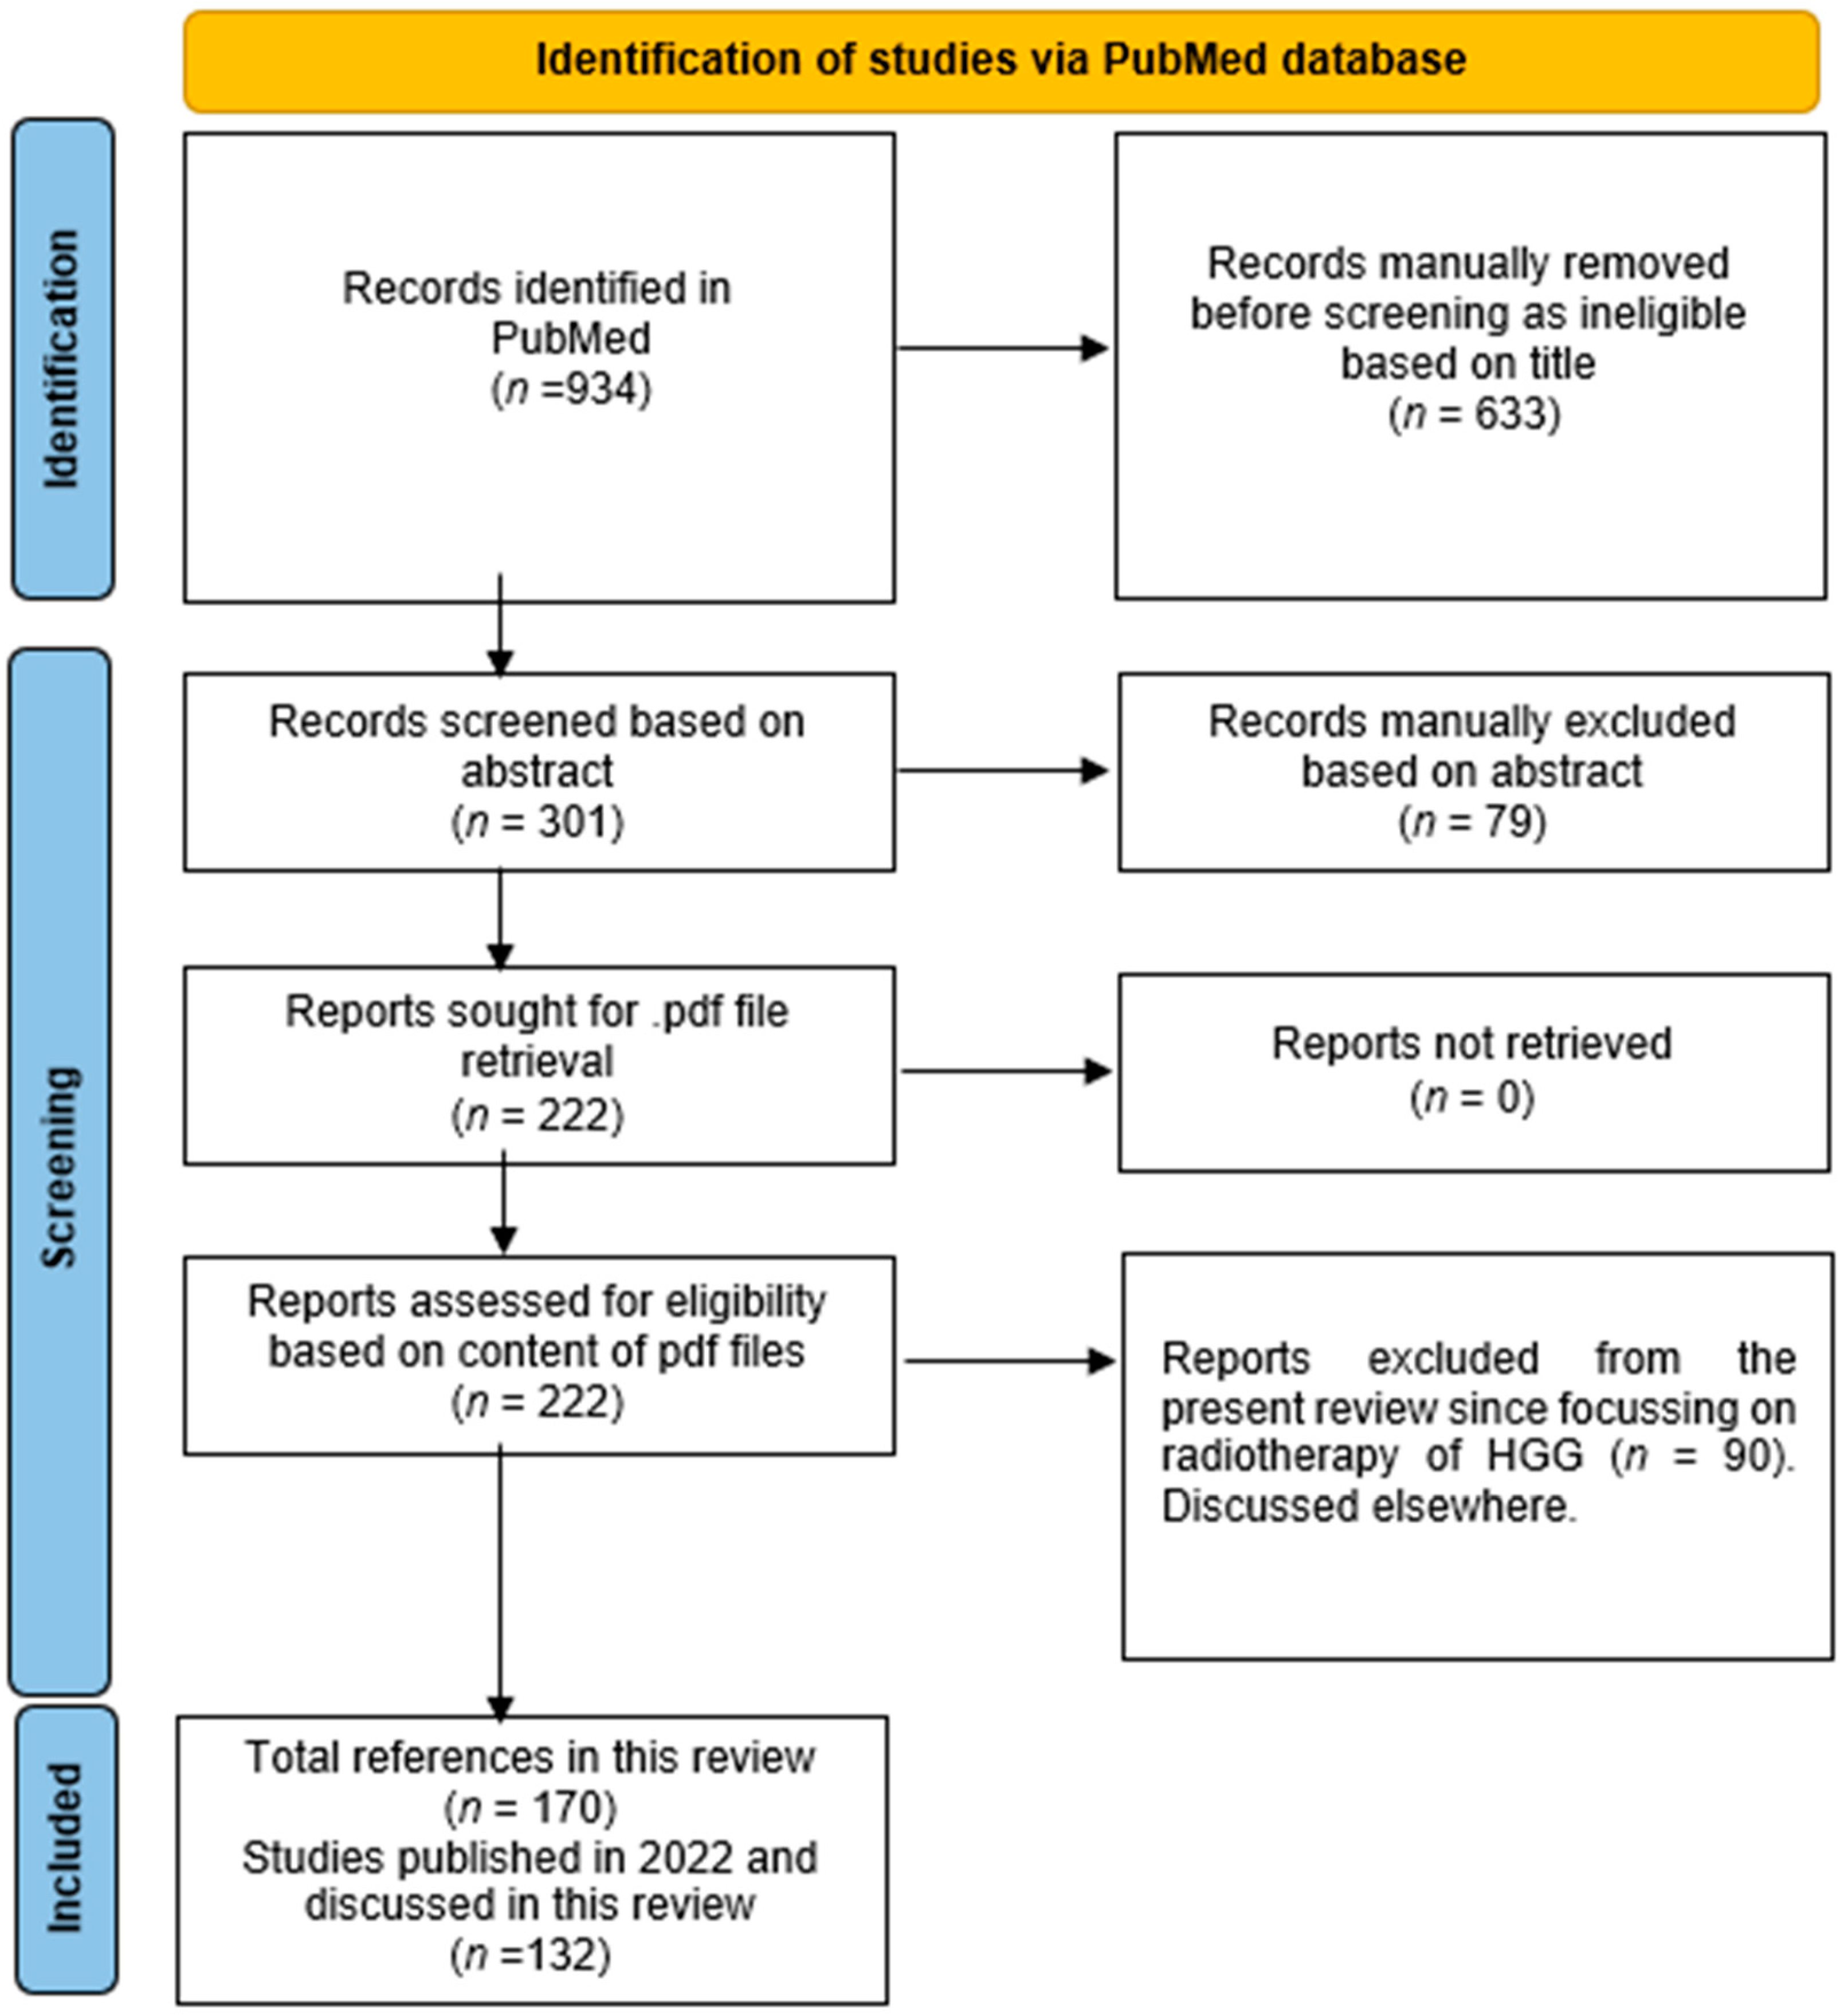

2. Materials and Methods

- Page, M.J.; McKenzie, J.E.; Bossuyt, P.M.; Boutron, I.; Hoffmann, T.C.; Mulrow, C.D.; Shamseer, L.; Tetzlaff, J.M.; Akl, E.A.; Brennan, S.E.; et al. The PRISMA 2020 Statement: An Updated Guideline for Reporting Systematic Reviews. BMJ 2021, 372, n71. [Google Scholar] [CrossRef]